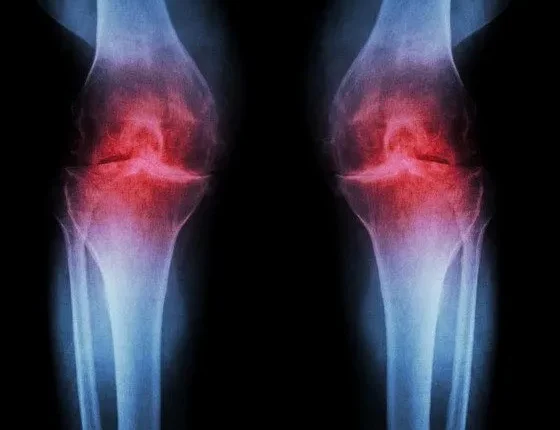

Η οστεοαρθρίτιδα είναι μια μορφή εκφυλιστικού πόνου στις αρθρώσεις που προκαλείται από τη φθορά τους. Oσο ο άνθρωπος μεγαλώνει, ο χόνδρος που προστατεύει τις επιφάνειες των οστών, χάνει την ελαστικότητά του και αρχίζει να φθείρεται.

Αυτό έχει ως αποτέλεσμα τα οστά να τρίβονται μεταξύ τους και αυτή η τριβή οδηγεί σε φλεγμονή των αρθρώσεων.

Η ΟΑ συνήθως επηρεάζει τις αρθρώσεις των χεριών και των ποδιών, συμπεριλαμβανομένων των δακτύλων, των καρπών, των γονάτων, των αστραγάλων και των γοφών. Το κάτω μέρος της πλάτης είναι επίσης μια συνηθισμένη πηγή πόνου της οστεοαρθρίτιδας.